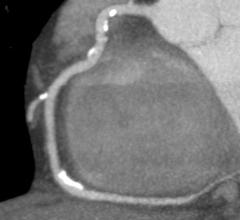

The importance of dealing with the epidemic of coronary artery disease (CAD) is well known, and the tools at our…

February 2, 2010 - Among noninvasive imaging tests for ruling out coronary artery disease (CAD), computed tomography…